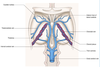

Venous drainage of the spinal cord

Follows basic pattern of arterial supply.

There are 6 longitudinal venous channels consisting primarily of anterior and posterior spinal veins which run in the midline.

There are sometimes incomplete/irregular bilaterally paired anterolateral and posterolateral veins situated near the sites of the ventral and dorsl nerve roots.

How do all of the veins of the spine drain

All drain via the anterior and posterior radicular veins into the internal vertebral venous plexus which is between the dura mater and vertebral periosteum.

With what does the internal venous plexus communicate

With an external venous plexus and thence with the ascending lumbar veins, the azygos and hemiazygos